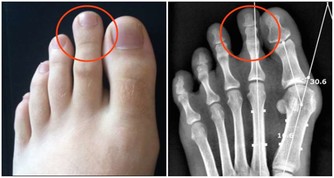

三是補養肺腎。中醫認為,按五行規律,夏天心火旺而肺金、腎水虛衰,要注意補養肺腎之陰。可選用枸杞子、生地、百合、桑葚以及酸收肺氣藥,如五味子等,可防出汗太過,耗傷津氣。